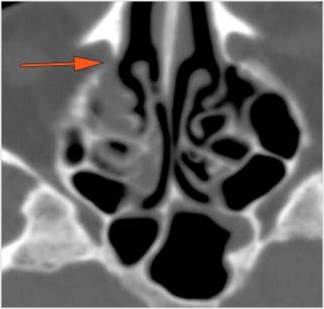

The extraconal orbital fat is abnormal.

There is a subperiosteal abscess or edema along the medial wall, roof or floor of the orbit.

There is bone erosion along the walls of the orbit.